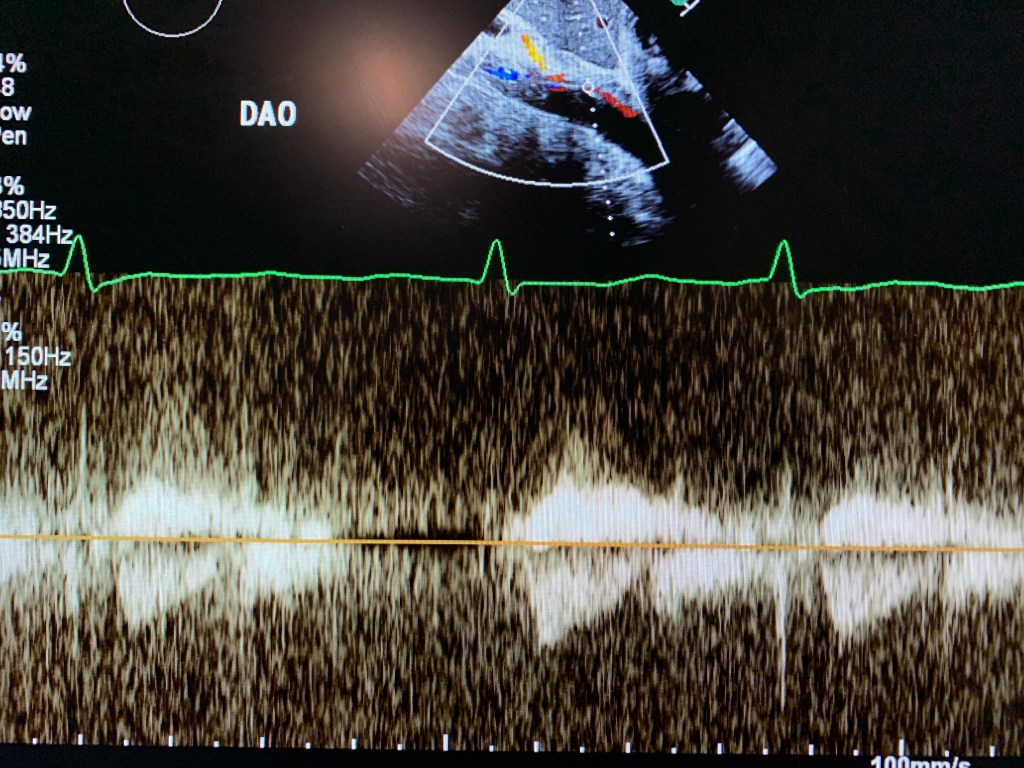

Echo:

Visualize PLAx view. Use high window and color Doppler.

Subcostal and suprasternal. Especially descending aorta.